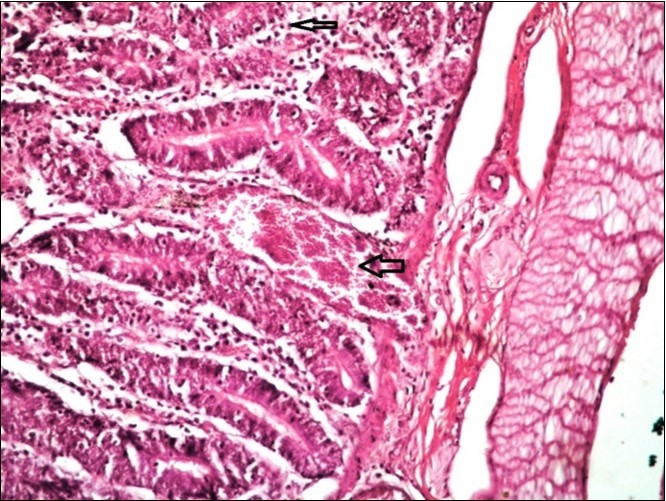

Figure 13.Small intestine (dead cattle less than 1 year old) showed hydropic degeneration, congested blood vessels, inflammatory cells (H&E, X 30).